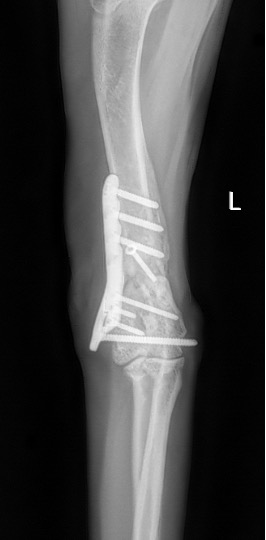

Notre préférence va vers le placement de deux plaques humérales : une médiale de la plus grande taille possible et l’autre latérale, généralement d’une taille inférieure à la première. Dans l’exemple 1 (chat européen), une plaque de 2 mm est utilisée médialement et une plaque de 1,5 mm latéralement. Dans l’exemple 2 (chien Malinois), une plaque de 3,5 mm est utilisée médialement et une plaque de 2,7 mm latéralement.

Exemple 2 :

Figure 5 : Post-Op Immédiat